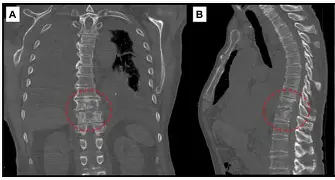

1. Spinal Tuberculosis (Pott’s Disease) Explained By Dr. Jitesh Manghwani

Spinal TB remains a common yet challenging condition in orthopedic practice. In this highly viewed session, Dr. Jitesh Manghwani simplifies a complex topic with excellent clinical clarity.

• Pathophysiology of spinal TB

• Key clinical features and red flags

• X-ray and MRI findings

• Complications like kyphosis and neurological deficits

• Principles of medical and surgical management

A must-watch for residents, students, and exam aspirants alike.